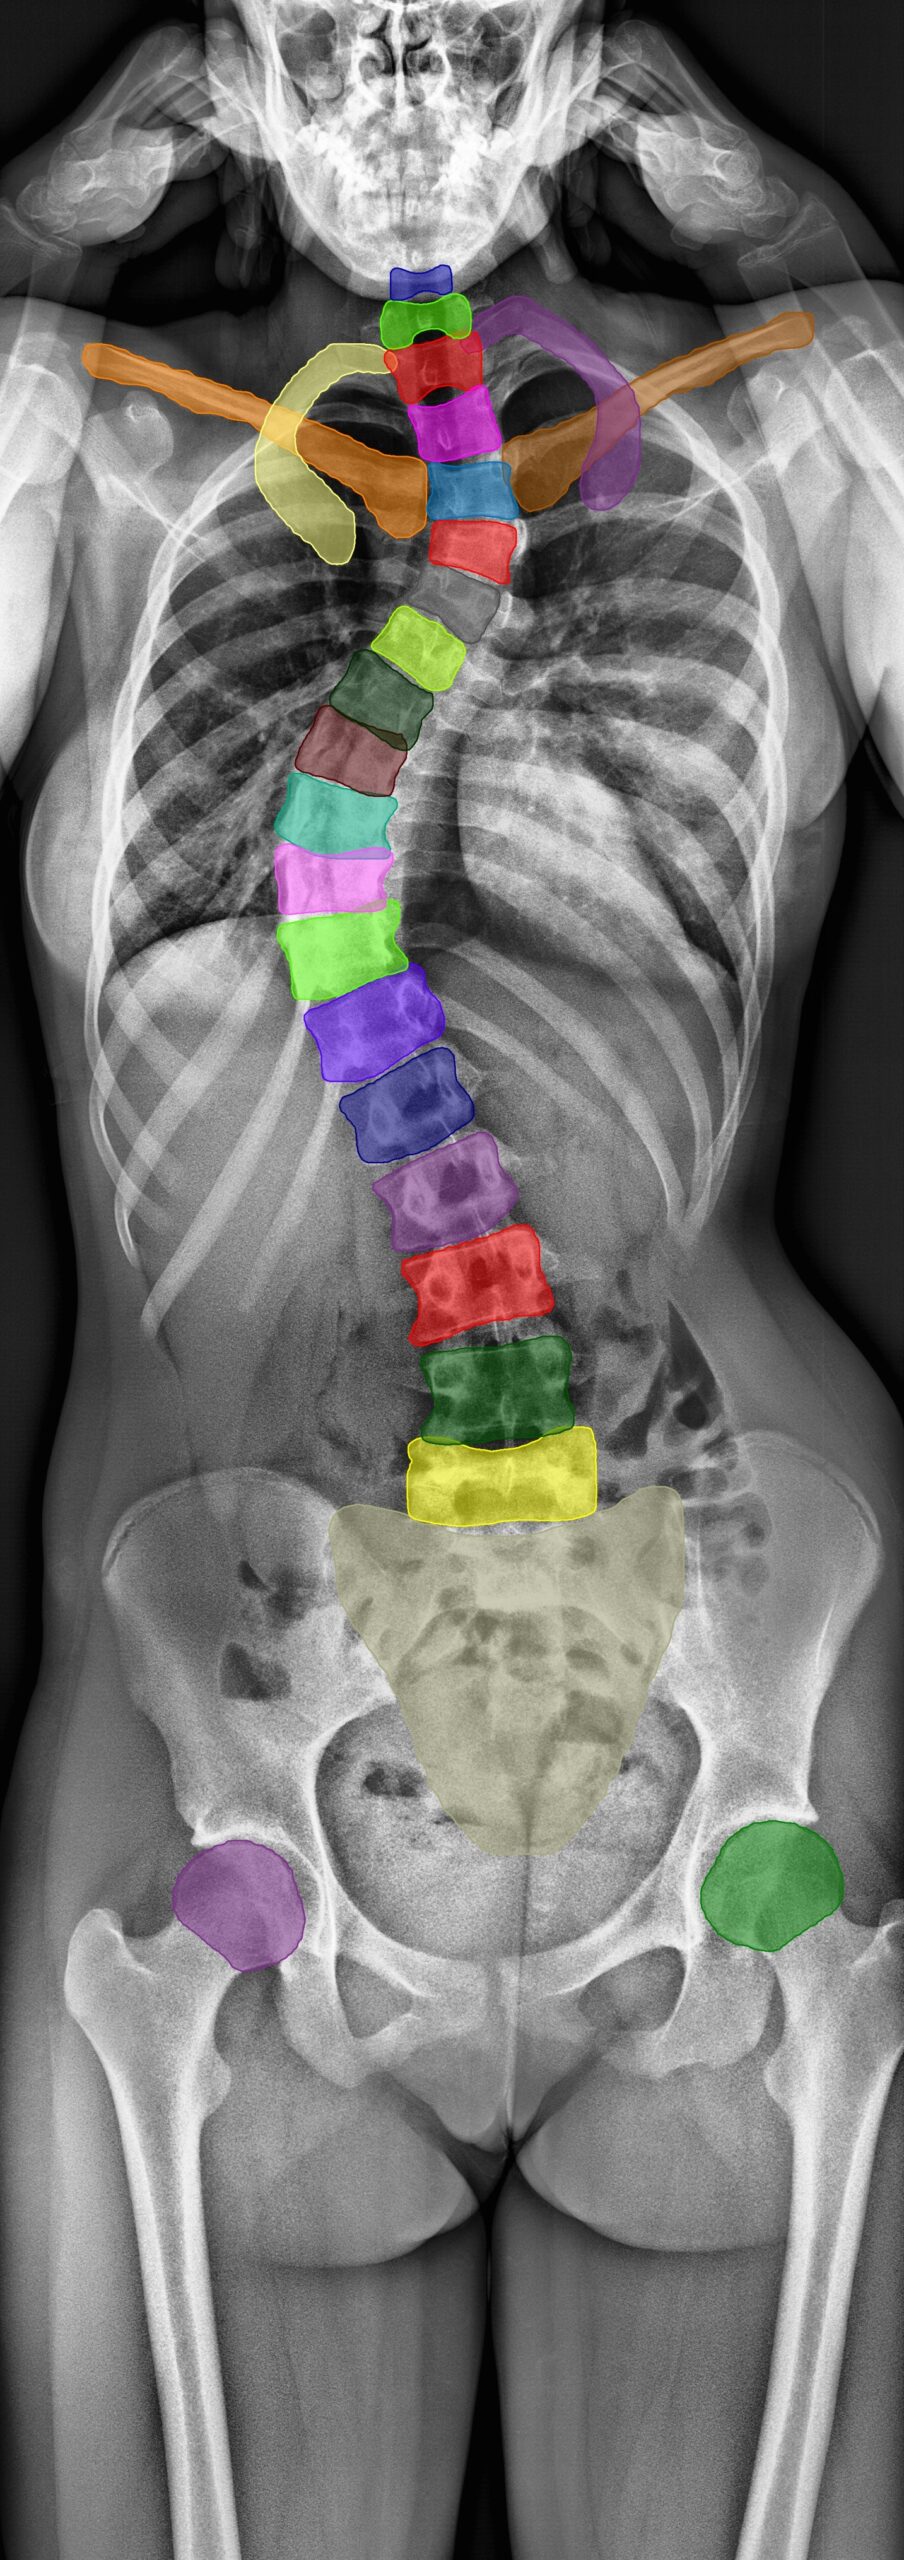

Radiographische Analysen nach Anatomie

Wir bieten umfassende radiographische Analysen für Wirbelsule, Hüfte und Knie und nutzen fortschrittliche Bildanalysetechniken, um präzise, regulatorisch konforme Messungen für Ihre klinischen Studien zu liefern.

Wirbelsäule

- Bewegungsumfang (Range of Motion, RoM)

- Rotationszentrum (Center of Rotation, CoR)

- Bandscheibenhöhe

- Anteroposterior-Instabilität

- Cobb-Winkel

- Zervikal- und Lumbarlordose

- Segmentale Bewegungsanalyse

- Fusionsbewertung

- Implantat-Subsidence

- Und über 100 weitere Parameter

Hüfte

- Pfannen-Anteversion

- Pfannen-Inklination

- Beckenobliquität

- Beinlängendifferenz

- Centrum-Collum-Diaphysenwinkel (CCD-Winkel)

- Femorales Offset

- Komponentenpositionierung (6 Freiheitsgrade)

- Polyethylen-Liner-Verschleiß

- Femurschaft-Subsidence

- Pfannenmigration

- Osseointegrationsbewertung

- Aufhellungssaum-Detektion

Die Functional X-Ray Analysis (FXA) Software unseres Imaging Core Labs analysiert genau und präzise über 150 radiologische Parameter der Wirbelsäule, Hüfte und Knie.